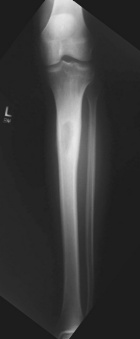

D.T. - 23 year old white male with a one month history of worsening left lower leg pain

Zoom image: Radiological image Radiological image.